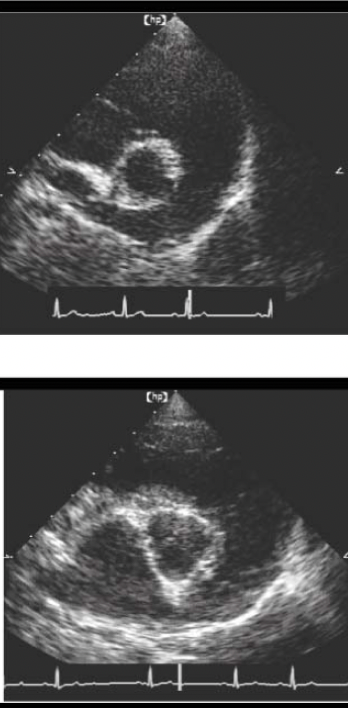

Name the echo view AND structures

RPS SHORT AXIS